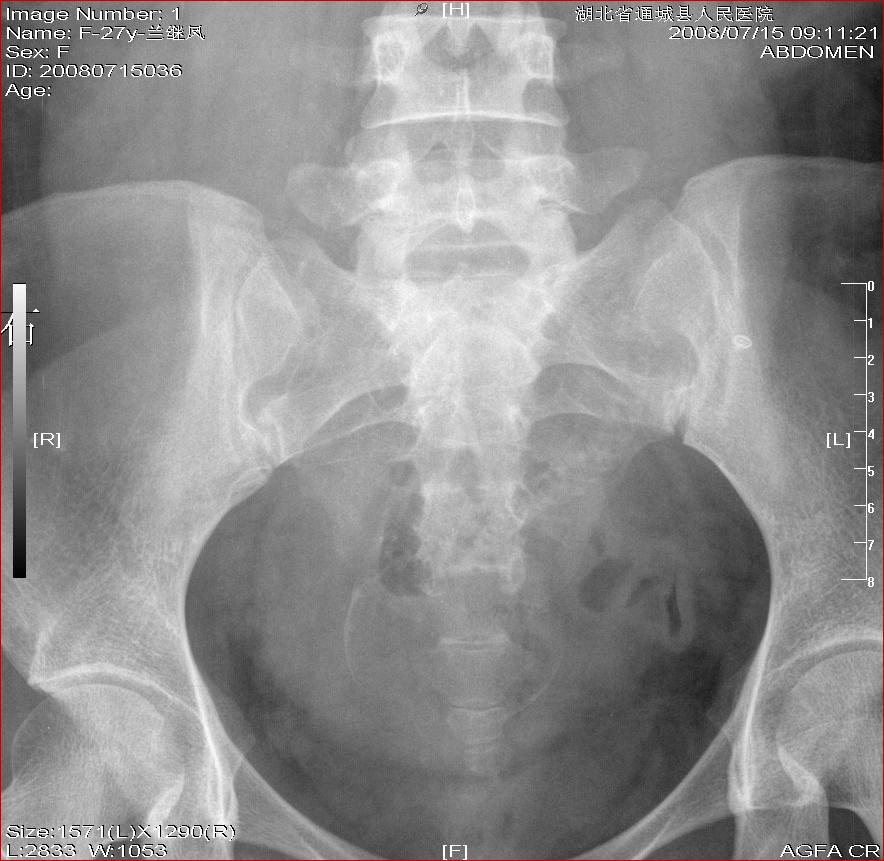

标题: X4684左肾结石+腹部胎儿

左肾结石+腹部胎儿

b超示双肾结石。孕妇及家人签字画押弃胎治石。才行平片检查,结果结石如此小。